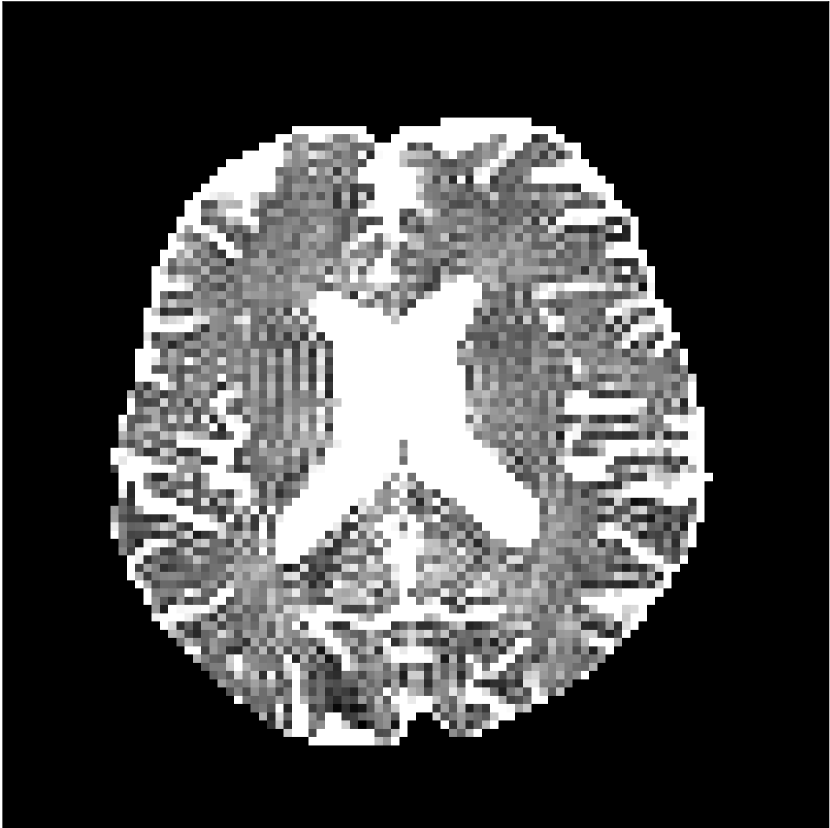

Figure 9 shows parameter maps for the different methods without partial Fourier (No PF) and with 5/8ths partial Fourier (5/8 PF). Mean diffusivities calculated from the raw DWI data (Raw) show notable noise and Gibbs ringing artifacts, while this is substantially removed with the state-of-the-art (SoA) method. However, the state-of-the-art method begins to lose its ability to compensate for the Gibbs ringing and resolution loss when partial Fourier is utilized in the acquisition. The effects of partial Fourier increases are primarily evident in the enlargement of the lateral ventricles and the presence of black lines in the vicinity of the lateral ventricles. The MCNN model is able to compensate somewhat for the ringing effects, but begins to introduce substantial artifacts at the 5/8ths partial Fourier factor, whereas the CCNN model continues to give high-quality mean parameter maps across all PF factors.

Raw

SoA

MCNN

Standard PF

CCNN

b=0𝑏0b=0 s/mm2

No PF

MD, μ𝜇\mum2/ms

5/8 PF

FA

MK

Figure 9: Parameter maps from various methods (with CSF masks for FA and MK). At the top are shown the b=0𝑏0b=0 images from Raw, state-of-the-art (SoA), MCNN, standard partial Fourier, and CCNN methods. Rows 2 and 3 show results for mean diffusivity, rows 4 and 5 show results for fractional anisotropy, and rows 6 and 7 show results for mean kurtosis. The SoA method and both deep learning methods perform well without partial Fourier acceleration; however, at the 5/8ths partial Fourier factor, substantial artifacts are present for all methods other than the CCNN method.

Similar trends are observed in the other diffusion parameter maps.